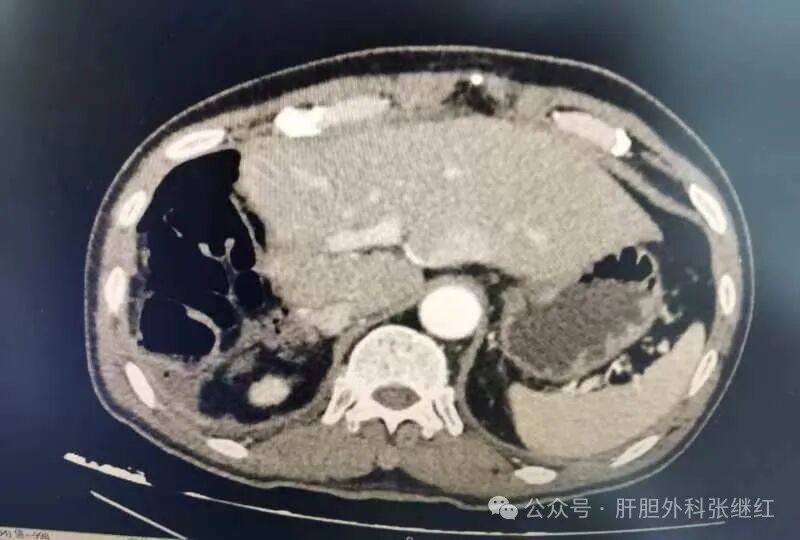

入院时CT